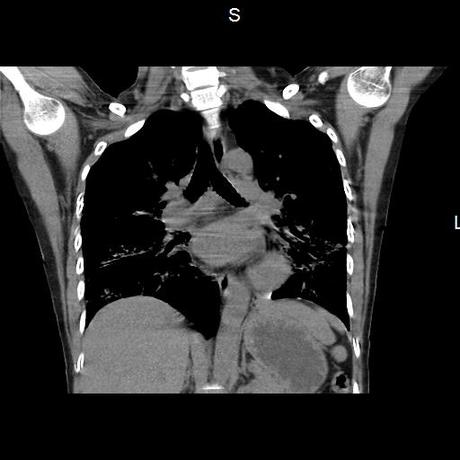

Se realiza volumen de tórax en fase simple, desde los opérculos torácicos hasta los hemidiafragmas, observándose:

El parénquima pulmonar con areas parcheadas difusas en vidrio despulido combinadas con otras areas hipodensas de baja atenuación debidas a atrapamiento aéreo y engrosamiento intersticial y zonas de fibrosis de predominio en lóbulos medios e inferiores de ambos pulmones.

- LOS HALLAZGOS PUEDEN ESTAR EN RELACIÓN A NEUMOPATIA INTERSTICIAL PROBABLE ETIOLOGIA HIPERSENSITIVA VS AUTOINMUNE/BACTERIANA/FUNGICA.